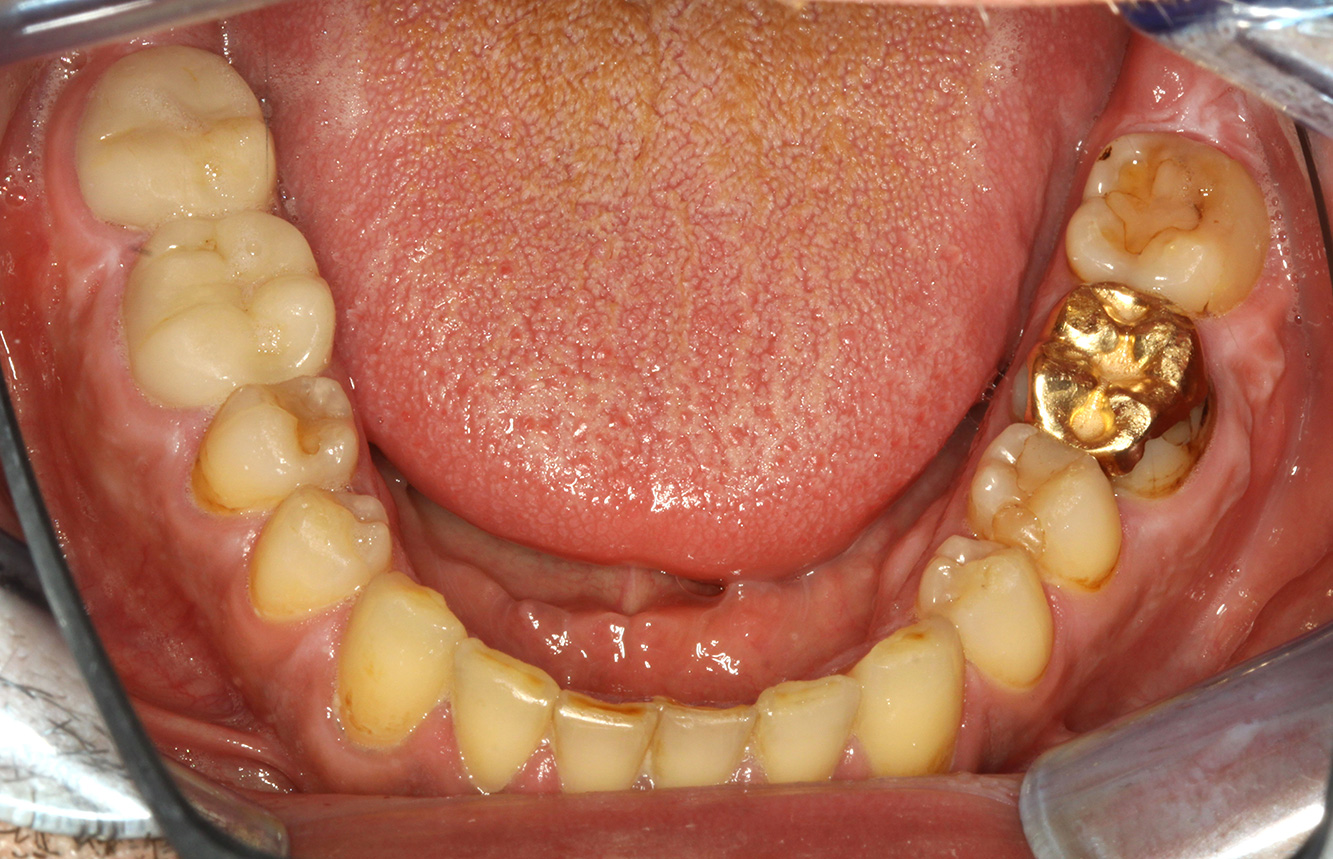

Casi di pazienti secondo l'IPCI seguenti studi di casi servono a mostrare l'interazione tra i fattori di bisogno e di rischio definiti per l'IPC così come gli effetti dei singoli fattori*. La paziente diabetica con una buona igiene oraleUna paziente diabetica di 51 anni con una buona igiene orale si presenta per una seduta di prevenzione. I valori di glicemia sono stabili con HbA1c = 6,2%, per cui si ritiene che la sua condizione possa essere sufficientemente gestita con la metformina (un farmaco per il trattamento del diabete). La paziente non presenta restauri esistenti o precedenti patologie orali. Sulla base dei referti disponibili si può constatare una gengivite nonostante una condizione altrimenti stabile. di più Case presentation: Complex Dental Prosthesis ManagementThe direct relationship between intraoral and general health, as well as the bidirectional influence that they may have on one another, is well-known (1,2). It is absolutely essential to consider both factors when planning preventive intraoral measures and treatment in the dental practice. The primary objective is the maintenance of patient health and quality of life from both dental and medical perspectives. more The (orally) healthy patient with implantsIn the medical history, the 55-year-old patient states that he has no systemic disease and is not taking any medication. The patient’s lifestyle is similarly unremarkable. The patient has a few tooth restorations and two implants (2nd and 4th quadrants). On the basis of current findings, gingivitis is identified in an otherwise stable periodontal condition on the reduced periodontium (stage III, grade A). more The healthy patient with pre-existing periodontal disease & peri-implantitisA 52-year-old patient presents at a preventive care session. The patient has no systemic disease and is not taking any medication. He has had various dental treatments and also has two active carious lesions. In addition, the patient has four implants (2nd, 3rd and 4th quadrants). He is revealed to have early periodontal disease (stage IV, grade B). His periodontal condition is stable; a probing depth of Probing depths (ST) of 5 mm is only evident at the implant in region 36. Gingivitis is also identified. more The Diabetic Patient with Pre-Existing PeriodontitisThis case report of a 52-year-old male with type 2 diabetes and periodontitis emphasizes personalized preventive measures and periodontal health maintenance to manage the moderate disease progression risk. more The 28-Year-Old Cigarette Smoker with Dental Erosions28-year-old patient, smoker, with erosions. The bidirectional relationship between oral and general medical health is very well known. It is no longer sufficient – and arguably even old-fashioned – to consider intraoral conditions in isolation. In order to create a personalized, case-specific preventive and patient profile, it is essential to take a detailed medical history and perform diligent examination of the general medical and intraoral health, as well as considering the two in combination. more Il paziente affetto da endocardite con lesioni cariose attiveIl paziente ha 39 anni e in passato è stato sottoposto ad un intervento per la sostituzione della valvola aortica dovuta a insufficienza valvolare ed endocardite. Assume regolarmente l'ASS 100 come anticoagulante. Per quel che riguarda lo stile di vita, il regime alimentare seguito dal paziente è classificato come “dieta che favorisce la formazione della carie”, per via del consumo regolare di cibi ad alto contenuto di zuccheri e dei sei-sette pasti consumati al giorno. La salute orale del paziente indica un rischio moderato di carie, con lesioni attive. Il rischio di parodontite è basso, tuttavia il paziente è affetto da gengivite. Si formulano quindi i seguenti consigli per il trattamento di profilassi. di più Il paziente trapiantato con iperplasia gengivaleSi presenta un paziente di 71 anni che ha subito un trapianto di reni e con anamnesi di ipertonia (ipertensione). Considerata la sua storia clinica, serve una terapia a lungo termine con ciclosporina che ha un effetto immunosoppressivo e amlodipina che è specifica contro l'ipertensione. Il paziente riporta anche gengive sensibili e sanguinanti. Per quanto riguarda invece lo stato di salute orale, il paziente ha un restauro, presenta un'iperplasia gengivale marcata, una parodontite allo stadio II, grado B con tasche attive e un'iniziale carie radicolare al dente 22 e in più mancano otto denti. Dalla valutazione del rischio di carie si evince un rischio moderato di carie (API 60). Per la seduta di profilassi si possono formulare i seguenti consigli per il trattamento. di più La paziente sana con precedente patologia parodontaleQuesta paziente di 68 anni non presenta alcuna patologia precedente né segue alcuna terapia che possano ritenersi rilevanti dal punto di vista odontoiatrico, e il suo stile di vita non comporta alcun rischio particolare. La paziente ha due impianti (3° quadrante, da cinque anni) e una precedente patologia parodontale (parodontite allo stadio IV, grado B) con perdita del dente. Al momento le condizioni parodontali sono stabili, tuttavia la parodontite aumenta in misura significativa le complicazioni biologiche degli impianti e c'è dunque il rischio di perdita dell'impianto (21). Per la seduta di profilassi si possono formulare quattro consigli. di più